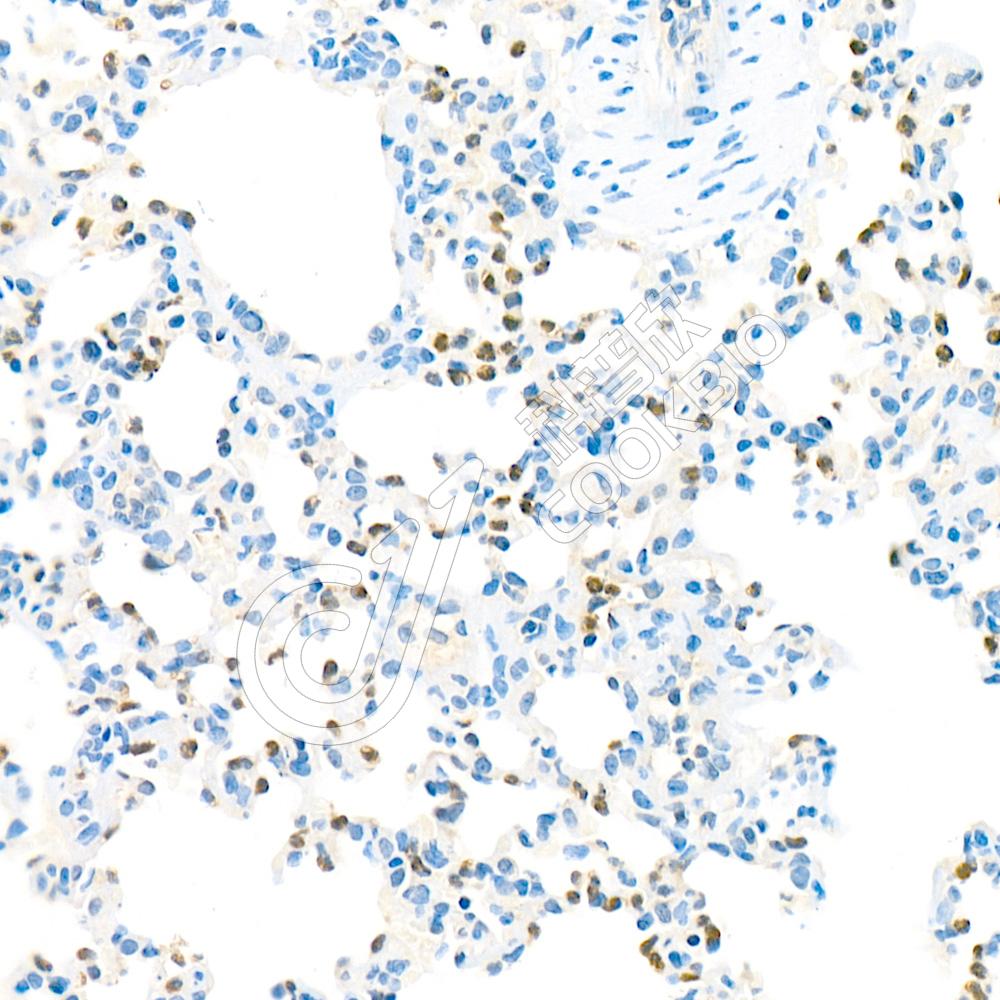

IHC检测ULK1蛋白(货号 K134740).

样品: 小鼠肺, 4%多聚甲醛 (货号KSG1101) 固定12-24小时.

抗原修复: 柠檬酸抗原修复液(干粉, pH 6.0) (KSG1201), 98℃, 20分钟.

—抗: 1: 1300稀释, 4℃ 孵育过夜.

二抗: S-vision免疫组化多聚二抗(山羊抗兔),即用型 (货号KB3906), 室温孵育20分钟.

样品: 大鼠肺, 4%多聚甲醛 (货号KSG1101) 固定12-24小时.